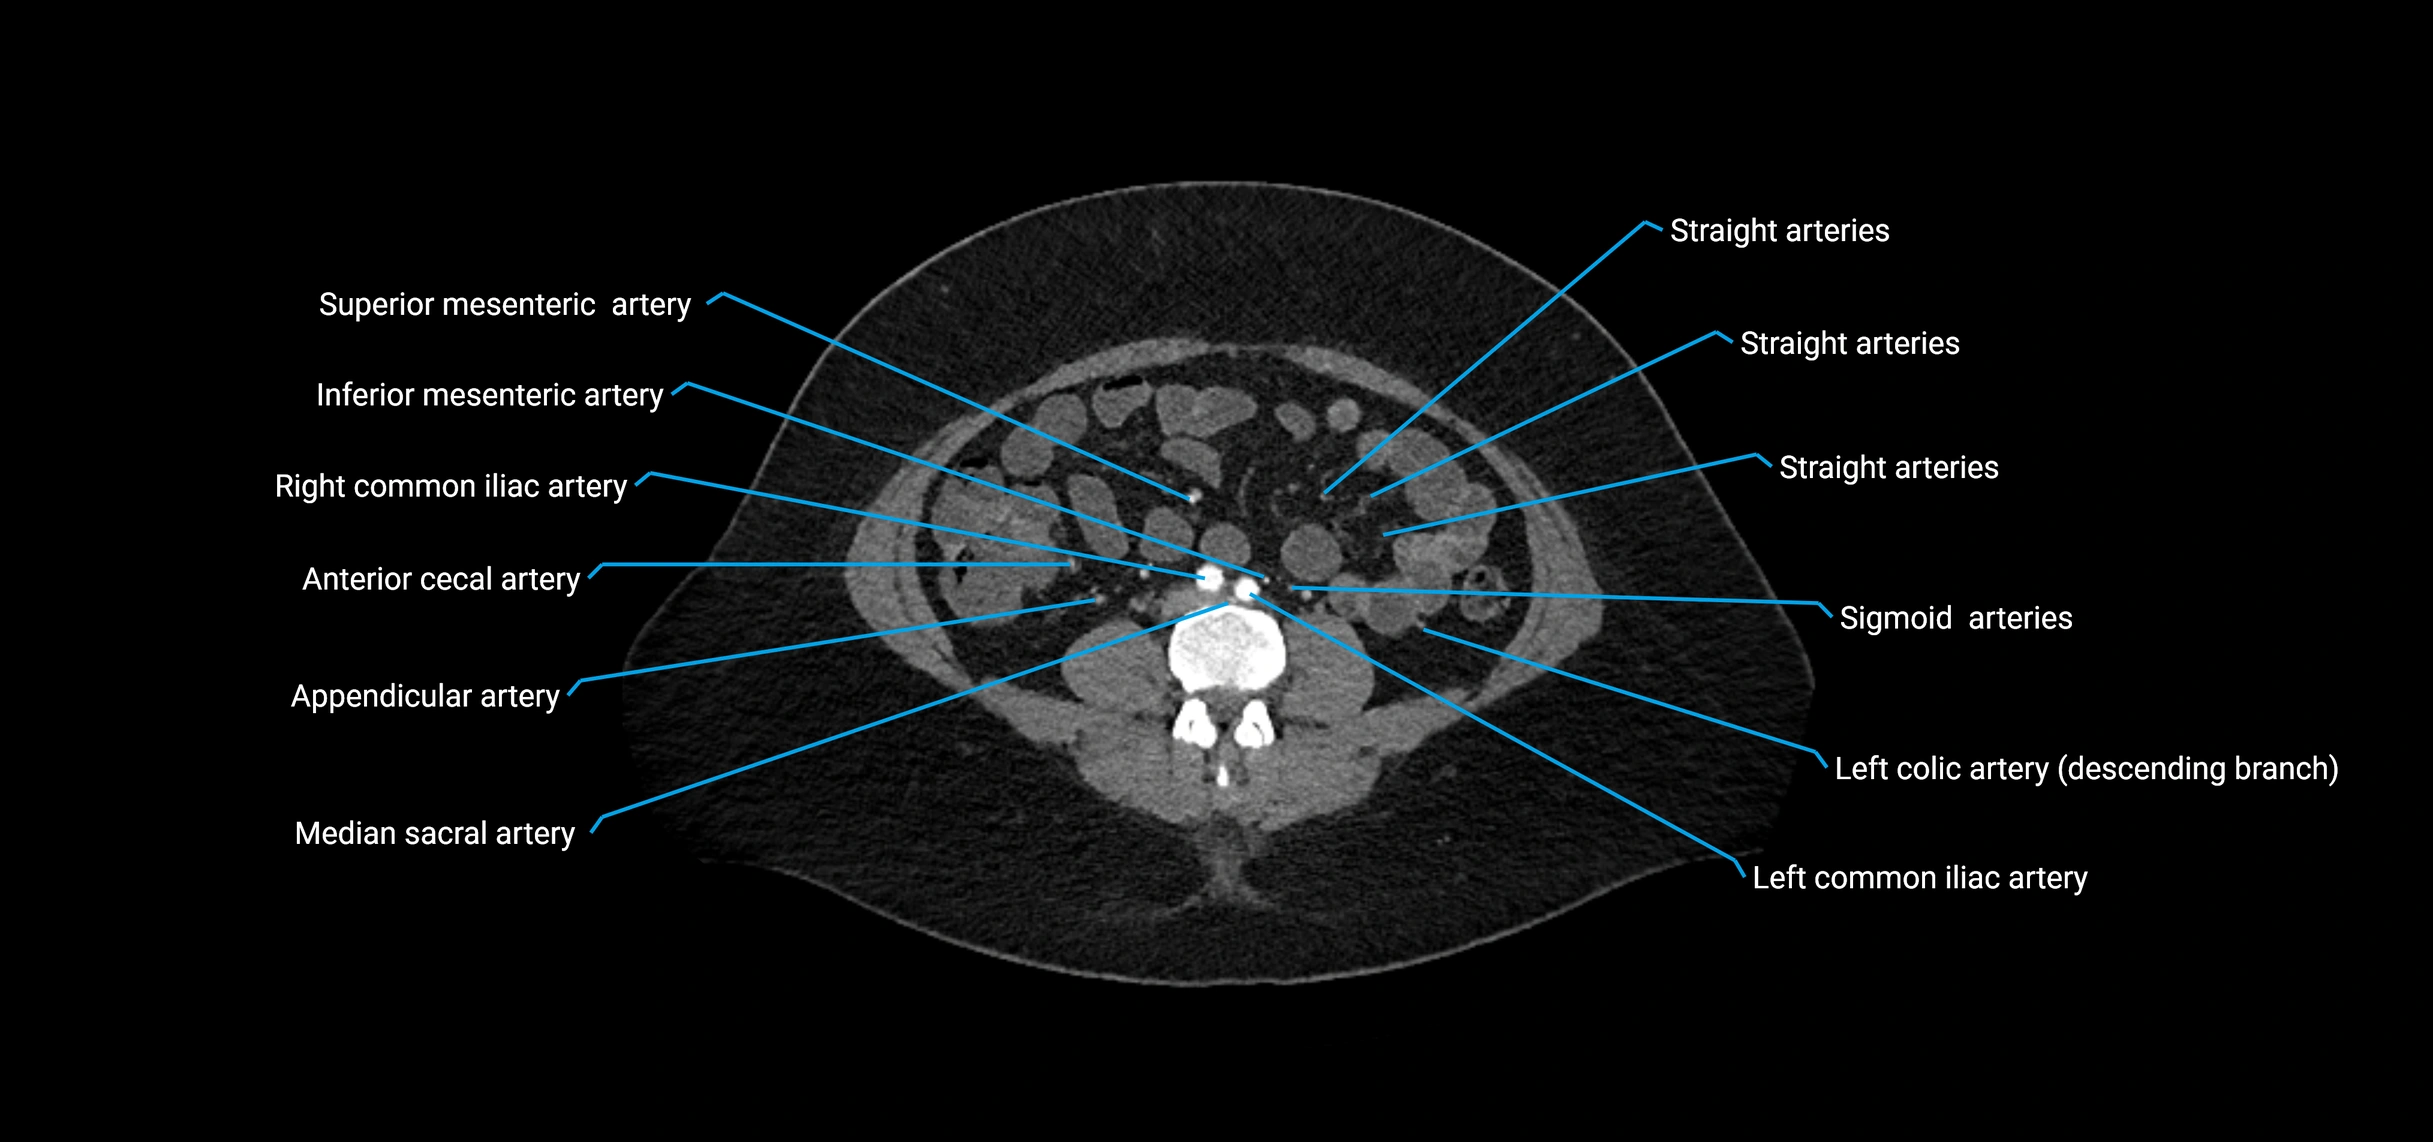

CT images

image

Contrast-enhanced CT (CTA):

• Gold standard for abdominal aortic imaging

• Provides excellent detail of lumen, wall, aneurysm, thrombus, and branch vessels

• Multiplanar and 3D reconstructions help in aneurysm measurement, stent graft planning, and dissection evaluation